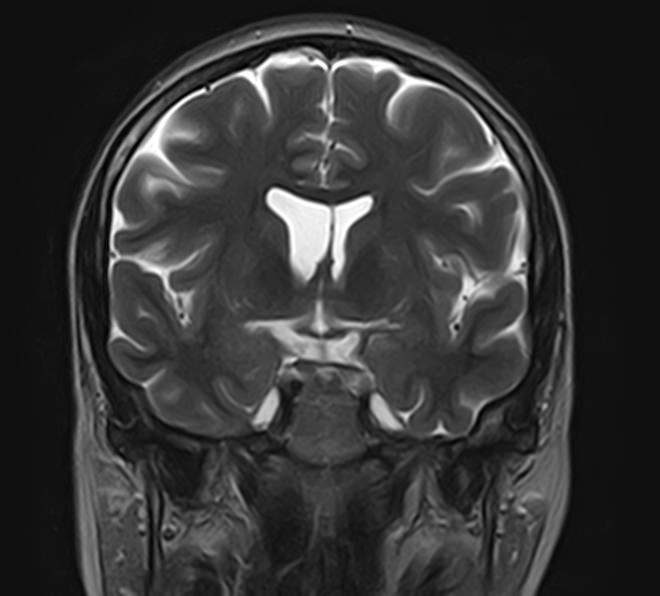

Для диагностики поражения черепно-мозговых нервов, а также оценки состояния окружающих их тканей и визуализации сосудистой сети головного мозга в клинике «Доступная медицина» проводится комплексное обследование МРТ головного мозга + Мр-ангиография головного мозга + МР-венография головного мозга + черепно-мозговые нервы. Данное обследование включает в себя несколько протоколов: стандартный – для оценки состояния всех структур головного мозга и дополнительные – для изучения очагов поражения черепных нервов и визуализации всей сосудистой системы головного мозга.

Исследования выполняются на современном высокопольном томографе экспертного класса TOSHIBA VANTAGE TITAN 1,5 Тесла, который использует разные режимы сканирования с толщиной среза от 1мм в различных плоскостях с последующей цифровой обработкой полученных данных для создания трехмерных изображений. МР-ангиография отображает состояние артериальной системы кровоснабжения головного мозга. МР-венография головного мозга позволяет детально изучить особенности венозного русла головного мозга.

Компьютерная программа обрабатывает данные, полученные при сканировании, и формирует объемные изображения как самого мозга, так и сосудистой системы в отдельности без прилегающих тканей. Методики применяются одновременно и взаимодополняют друг друга.

Данное комплексное исследование в большинстве случаев проводится с контрастным усилением, которое необходимо для улучшения визуализации черепно-мозговых нервов. Для этого внутривенно вводится препарат, содержащий гадодиамид (соли металла гадолиния) для получения изображений с высокой четкостью и контрастностью, что способствует ранней диагностике заболеваний головного мозга.